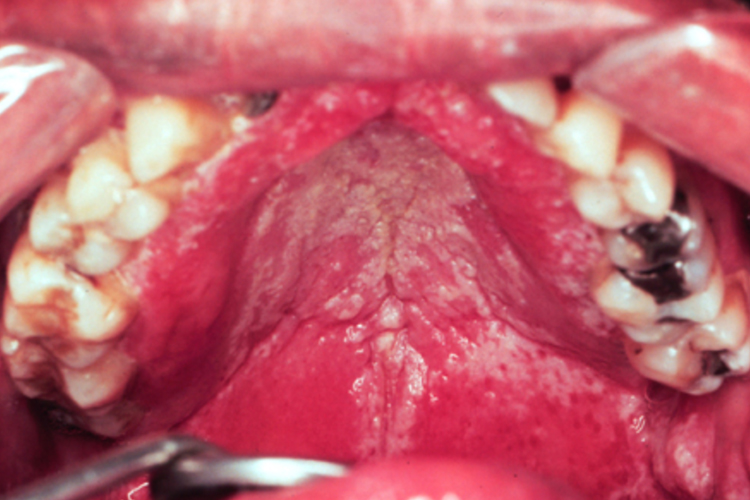

鹅口疮:鹅口疮表现为口腔黏膜表面覆盖白色乳凝块样小点或小片状物,可逐渐融合成大片白斑,不易擦去,周围无炎症反应,强行剥离后局部黏膜潮红、粗糙,可有溢血,不痛、不流涎。

义齿性口炎:白色念珠菌感染导致的义齿性口炎,损害部位常在上颌义齿腭侧面接触的腭、龈黏膜,黏膜呈亮红色水肿,或有黄白色的条索状或斑点状假膜。